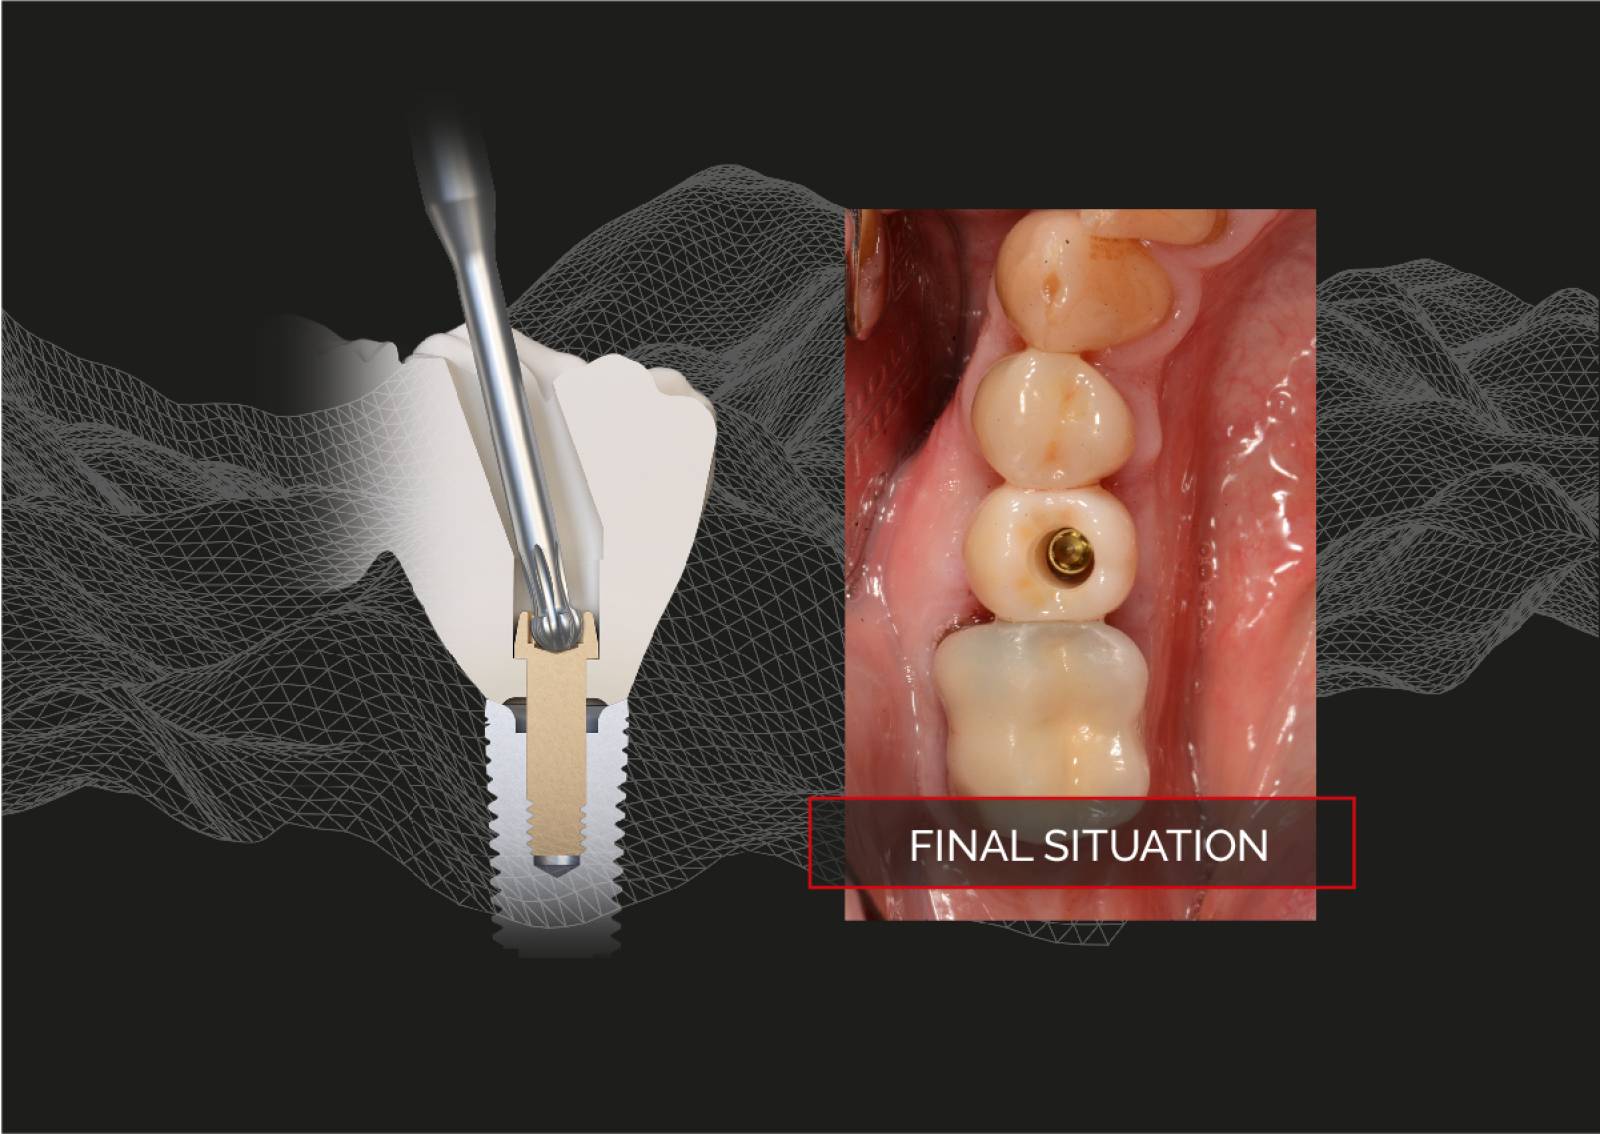

PROSTHETIC

Handling of the matrix® prosthetics.

The precision of matrix® prosthetics.